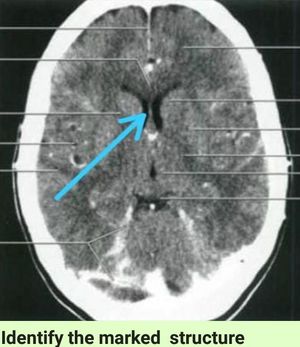

Identify

Lateral ventricles